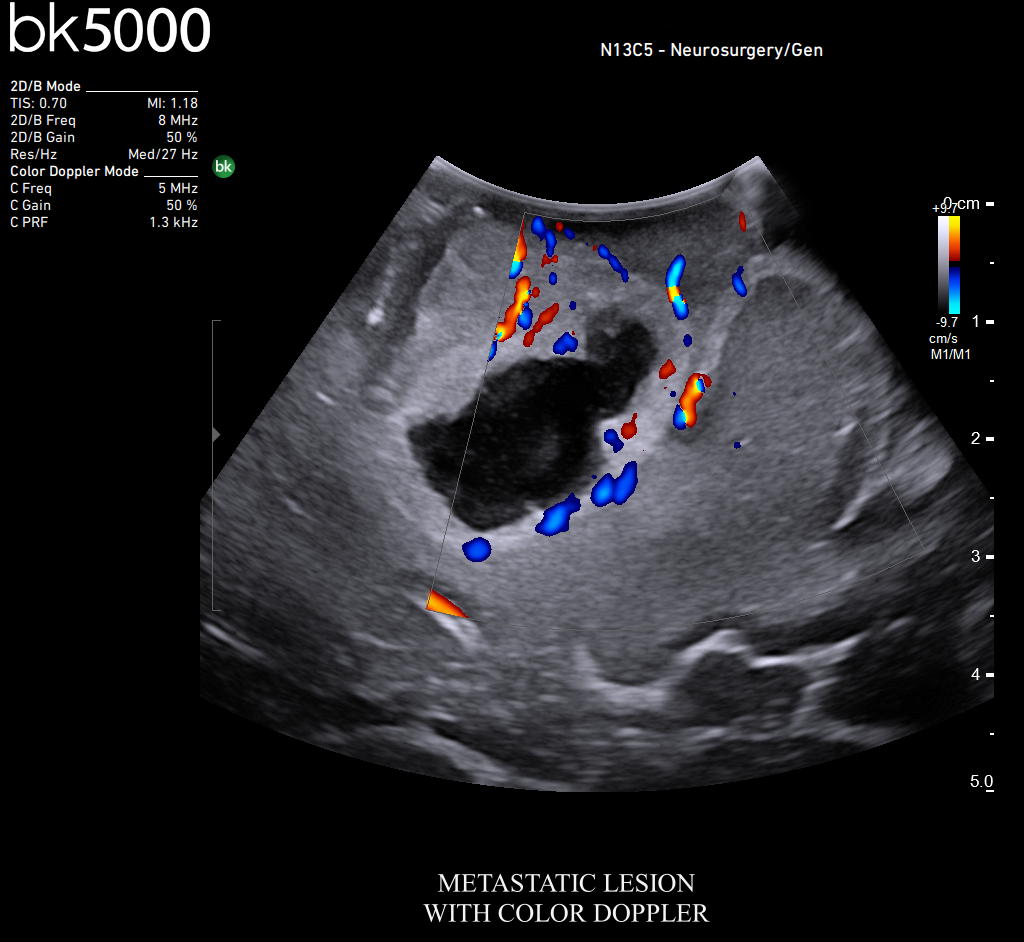

Ultrasound can improve neurosurgical procedures by helping you navigate and identify lesions and anatomical structures in real-time. This is particularly important as the data obtained from a preoperative CT or MRI scan can be outdated at the time of surgery. The bk5000 neurosurgical system provides the highest quality images that allow you to clearly see the margins of a lesion and to determine the best course of action. Using advanced graphics processing technology, this powerful system provides immediate, auto-optimized images that allow you to see the information you need, faster.

The specialized, high-resolution, sterilizable neurosurgery transducers enable you to obtain detailed images of the brain and spinal cord. They have a convenient Smart™ button that lets you activate the transducer, then freeze, store or print the images at the press of a button. Disposable, easy-to-use needle guides assist with targeting lesions.